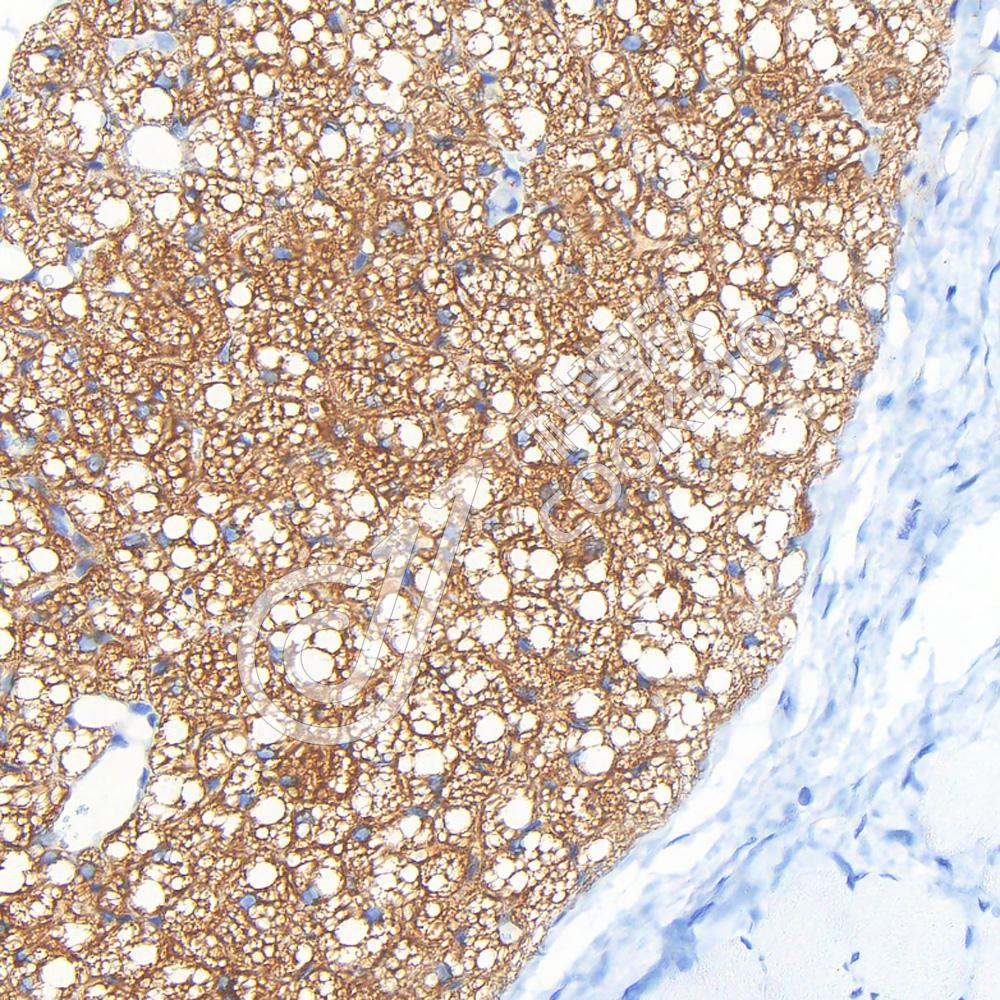

IHC检测UCP1蛋白(货号 K5456522).

样品: 小鼠棕色脂肪, 4%多聚甲醛 (货号KSG1101) 固定12-24小时.

抗原修复: 柠檬酸抗原修复液(干粉, pH 6.0) (KSG1201), 高压锅均匀喷气计时2分钟.

—抗: 1: 700稀释, 4℃ 孵育过夜.

二抗: S-vision免疫组化多聚二抗(山羊抗兔),即用型 (货号KB3906), 室温孵育20分钟.